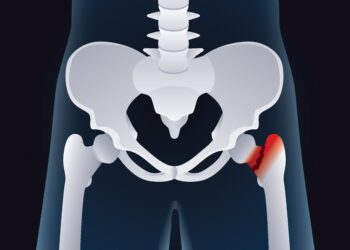

Skaityti daugiauDetailsHemartrozė – tai būklė, kai kraujas kaupiasi viename iš sąnarių. Dažniausiai ši problema iškyla dėl įvairių sveikatos sutrikimų, traumų ar...